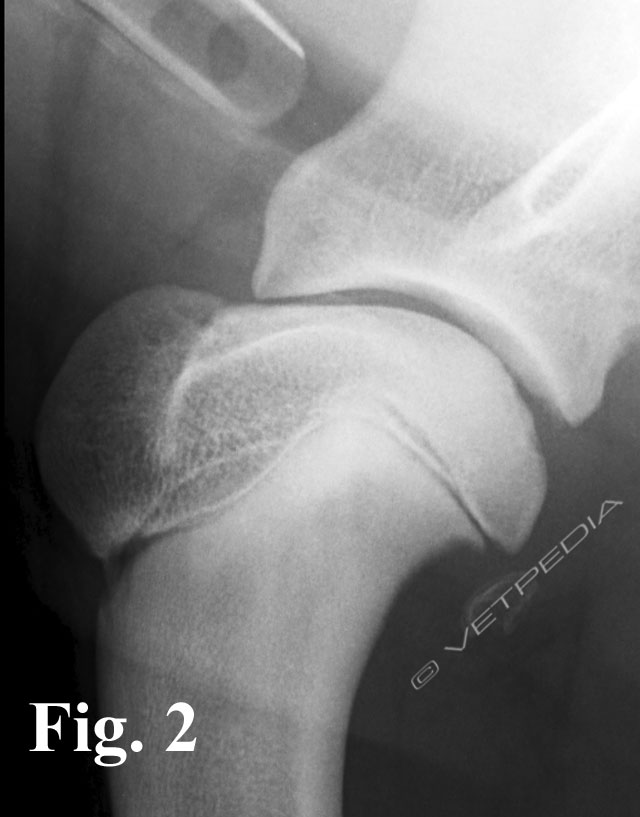

Con il cronicizzarsi della lesione si osservano fenomeni riparativi irregolari a carico del difetto osteocondrale, seguiti dalla formazione di osteofiti a livello della porzione caudale della testa omerale e della glena caudale (Fig. 7).